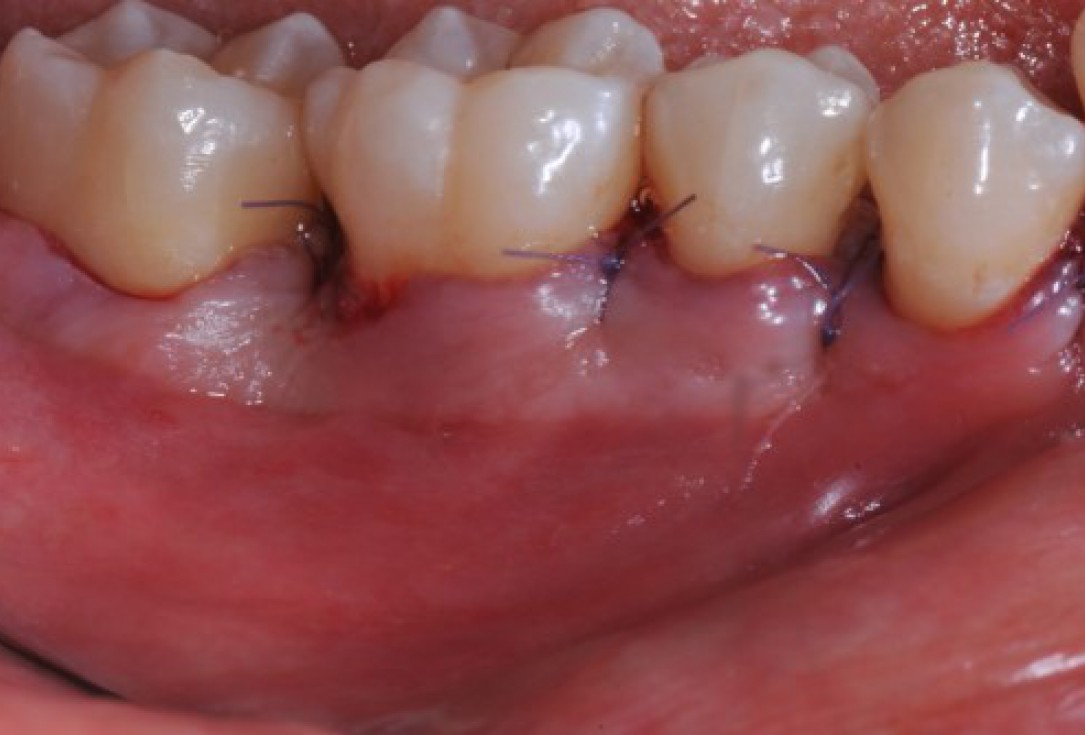

Radiographic view before periodontal regenerative therapy with Straumann® Emdogain®. A deep intrabony defect appeared mesially and distally on the left mandibular first premolar. Pre-surgical probing measured 8 mm. The defect morphology presented as well-contained.